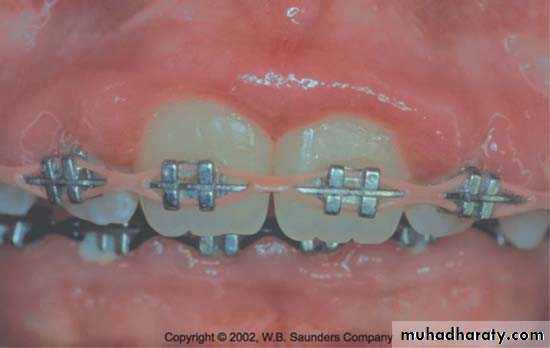

Periodontal Complications Associated with Orthodontic Therapy

Orthodontic therapy may affect the periodontium by favoringplaque retention, by directly injuring the gingiva as a result of overextended bands, and by creating excessive forces, unfavorable

forces, or both on the tooth and supporting structures.

Retention of plaque; Increase in Prevotella intermedia , Actinomyces odontolyticus, Actinobacillus actinomycetcomitans with decrease in aerobic facultative bacteria.

Oral hygiene improvement with evaluation of periodental diseases at each recall visits are mandetory from periodontal point of view.

Irritation from orthodontic bands-start at early eruption of tooth .

-bands should not extend up to gingival tissue

-Forceful impingement lead to detachment of gingiva from tooth.

Gingivitis & enlargement associated with orthodontic treatment & poor oral hygiene .